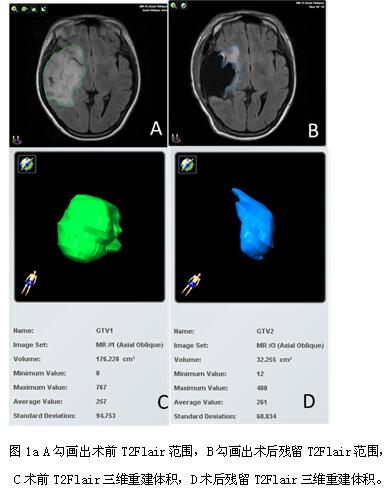

3. T2Flair术前、术后及切除范围计算方法 收集患者术前、术后48小时内MRI-Flair图像,术前、术后MRI图像导入德国Brainlab计划系统,采用Brainlab-iPlan软件定量计算术前、术后残余T2Flair体积(如图1a),并计算出T2flair 切除程度。

1.肿瘤T2Flair术前及术后体积 47例患者术前T2Flair中位体80.01cc(4.28ml~278.62ml),术后残留T2Flair中位体积37.58cc(1.41ml~227.91ml);

长期以来,习惯将肿瘤的切除程度划分为全切、次全切、部分全切及活检四个等级。但不同研究对这4个等级的定义并不统一,存在一定主观上的偏差。采用Brainlab-iPlan软件定量计算出术前及残余T2Flair体积,能较为客观、准确地描述出肿瘤的切除程度。